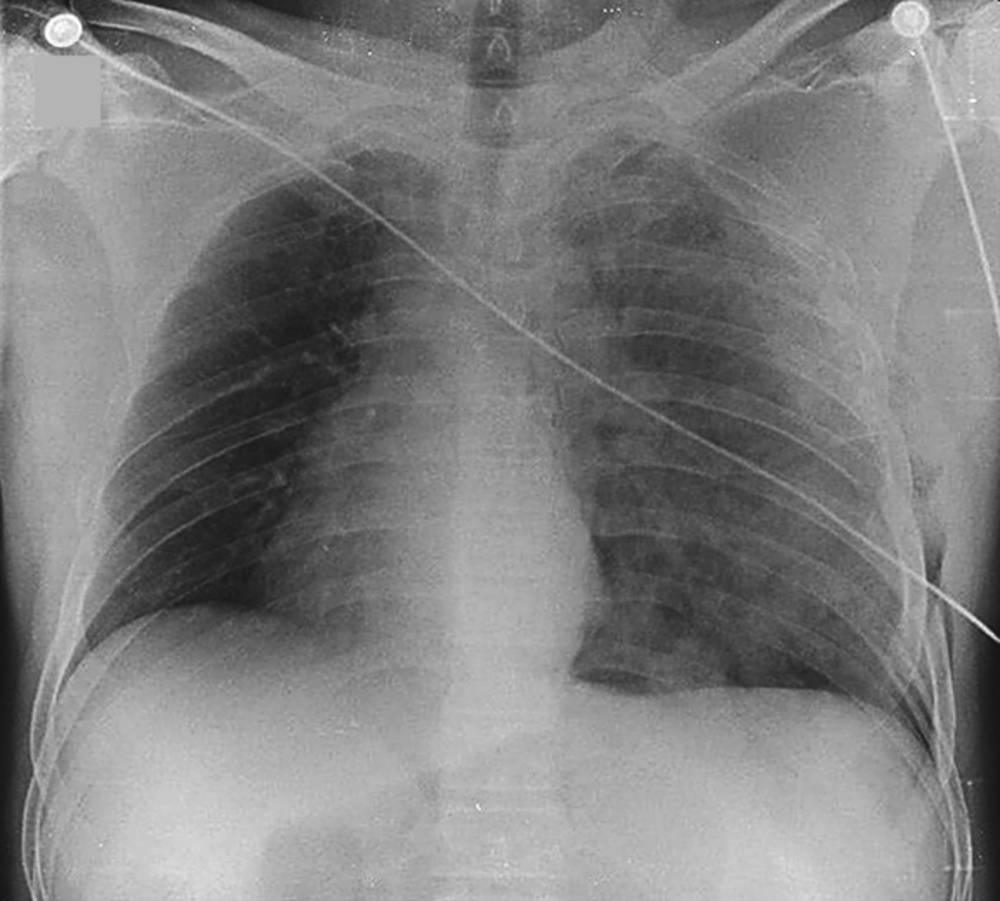

Patient with Chest Trauma Related to a Motorcycle Accident Post category:Spot Diagnosis Post published:March 26, 2022 Share on Facebook Share on X (Twitter) Share on Pinterest Share on Email Share on Reddit Chest X-Ray of a Patient with Chest Trauma Related to a Motorcycle Accident A 48-year-old man was referred to the emergency department for chest trauma related to a motorcycle accident. What is the Diagnosis ? CLICK FOR FULL CASE AND ANSWER Share on Facebook Share on X (Twitter) Share on Pinterest Share on Email Share on Reddit Read more articles Previous PostHyperpigmented Square on Lower Back Next PostPatient with Symptoms of Eye and Ear Pain You Might Also Like Patient with Acute Dyspnea and Chest Pain and a History of Peptic Ulcer April 10, 2022 Annular, Scaly, Blistering, Violaceous Plaque after use of Antibiotic August 19, 2021 Nonpruritic, Well-Circumscribed, Scale-Covered, Erythematous Plaques on Palms and Soles November 3, 2021